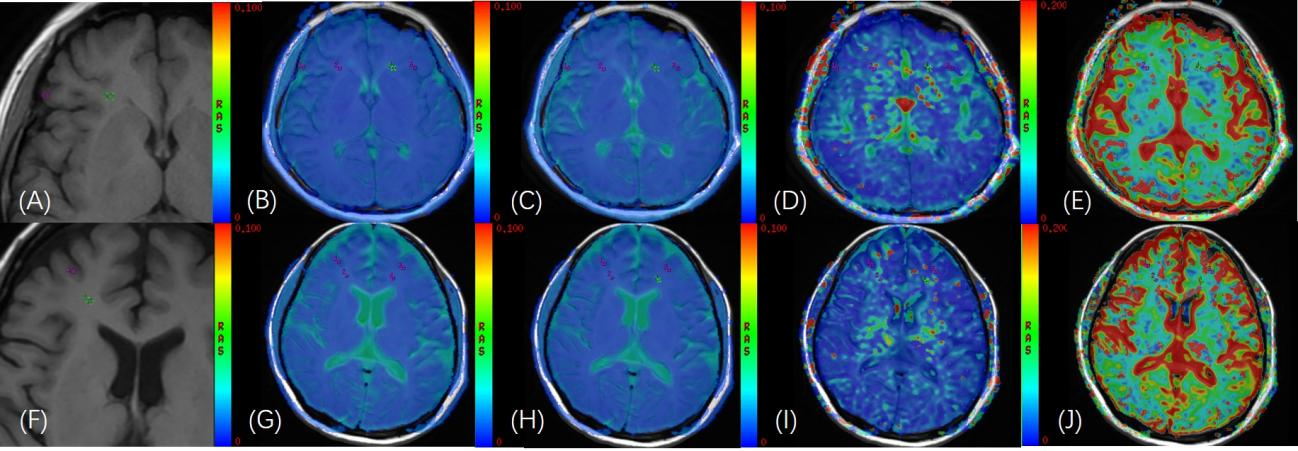

图1����:正常志愿者(A)头颅轴位 T1WI 图像���;(B)-(E)在轴位 IVIM功能像(sADC�����、D����、D*����、f图)与轴位 T1WI 融合图像上勾画双侧额叶的灰质����、白质��,(灰质:f =15.8%;白质:f =18.1%)�����,ROI面积为8mm2���。AL 患者(F)头颅轴位 T1WI 图像��;(G)-(J)在轴位 IVIM 功能像(sADC����、D���、D*��、f图)与轴位 T1WI 融合图像上勾画双侧额叶的灰质���、白质���,(灰质:f =1.37%;白质:f =6.5%)����,ROI面积为8mm2��。